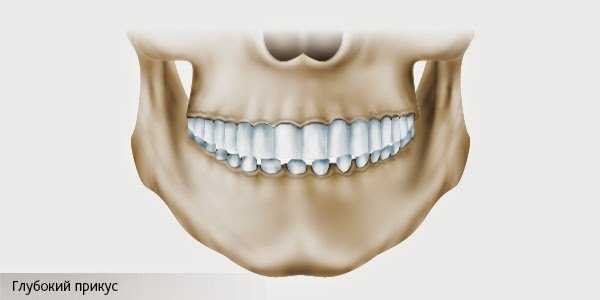

Глубокий прикус – это функциональное нарушение, при котором верхние резцы перекрывают нижние не менее чем на 1/3 поверхности коронки при смыкании зубных рядов. Заболевание может привести к расшатыванию и выпадению зубов в относительно раннем возрасте.

Глубокий прикус – вертикальная аномалия окклюзии, характеризующаяся увеличением перекрытия нижних резцов верхними более чем на треть высоты их коронок и нарушением режуще-бугоркового контакта. Глубокий прикус сопровождается нарушением эстетики лица, затруднением жевания, дефектами речи, хронической травматизацией слизистой оболочки неба и десны, повышенной стираемостью зубов, дисфункцией ВНЧС. Глубокий прикус диагностируется с помощью анализа диагностических моделей челюстей, ТРГ, ортопантомограммы, фотографий лица. Лечение глубокого прикуса проводится с использованием ортодонтических конструкций (вестибулярных пластинок, функциональных аппаратов, трейнеров, брекет-систем и др.).

Глубокий прикус – разновидность неправильного прикуса, при котором во время смыкания челюстей отмечается значительное вертикальное перекрытие резцов нижнего ряда резцами верхнего ряда. Глубокий прикус относится к числу наиболее частых аномалий прикуса, с которыми сталкивается врач-ортодонт в своей повседневной практике. По различным данным, популяционная частота глубокого прикуса колеблется от 6 до 51%. В структуре аномалий окклюзии глубокий прикус составляет около 20%. В стоматологии глубокий прикус иногда обозначается терминами «травмирующий прикус», «снижающийся прикус», «глубокое резцовое или фронтальное перекрытие», «глубокая резцовая окклюзия или дизокклюзия».